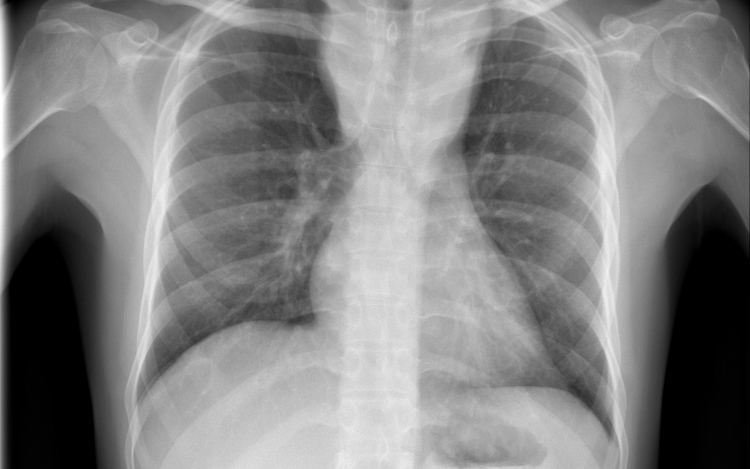

Átlagosan 4,3 százalékkal csökkent az új tuberkulózisos (tbc-s) esetek száma 2010 és 2014 között az Egészségügyi Világszervezet (WHO) 53 országot magába foglaló európai régiójában.

A becslések szerint 2014-ben 340 ezer európai betegedett meg tuberkulózisban, ami százezer emberre vetítve 37 esetnek felel meg. Azzal, hogy 2010 és 2014 között átlagosan 4,3 százalékkal csökkent az új esetek száma, az európai régió teljesítette azt a millenniumi fejlesztési célt, hogy 2015-re visszafordítja a tbc terjedésének tendenciáját.

Magyarországon biztonságos a tbc-re vonatkozó epidemiológiai helyzet: 2014-ben nyolc új eset jutott százezer lakosra, és az előzetes adatok szerint ugyanez igaz a 2015-ös évre is. Így a WHO Magyarországot az alacsonyan átfertőzött országok között tartja nyilván. Alacsony a multirezisztens esetek száma - 2014-ben hét új esetet észleltek -, valamint a gyermekkori megbetegedéseké is: 2014-ben hat 14 éven aluli gyermek betegedett meg.

Az európai régióban ugyanakkor továbbra is nehezíti a tbc felszámolását a multirezisztens tbc és a tbc magas előfordulási aránya a lakosság sérülékeny csoportjaiban (hajléktalanok, kábítószer- és alkoholfüggők, magas fertőzöttségi arányú országokból érkező migránsok) - áll a közleményben. Ezeknek a szegény és marginalizálódott csoportoknak az eléréséhez az ECDC tudományos útmutatást adott ki a közelmúltban.

A WHO a legnagyobb kockázatnak kitett csoportok célzott tbc-szűrését javasolja, Magyarországon 2014 óta eszerint szervezik meg a kötelező tüdőszűrést.